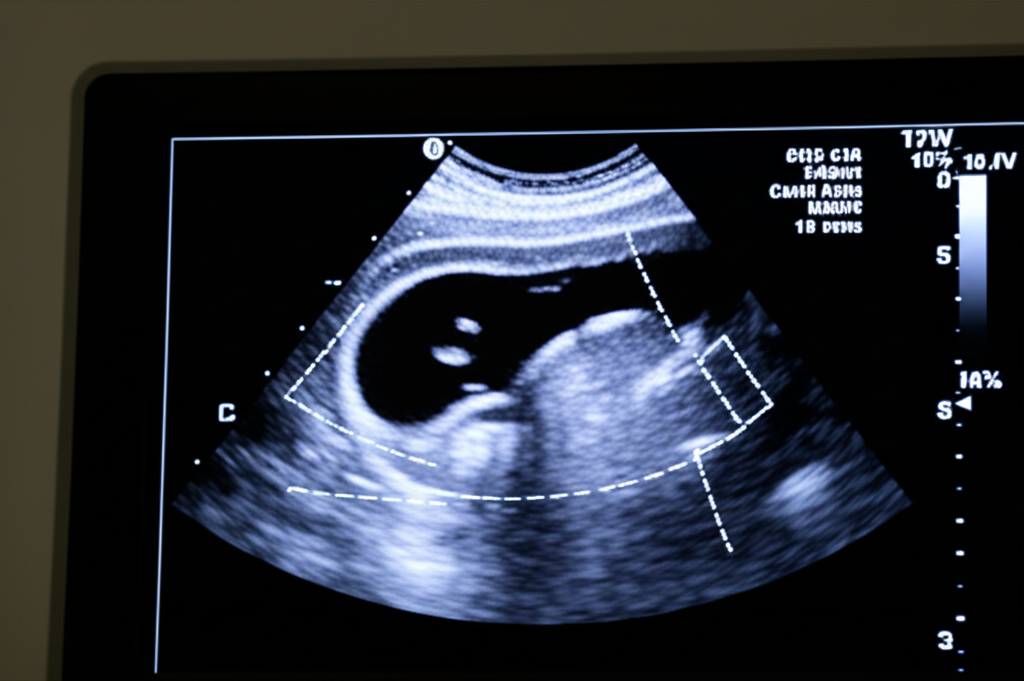

경동맥 초음파 검사란 무엇일까요?

경동맥 초음파 검사는 초음파를 이용하여 경동맥의 상태를 확인하는 검사입니다. 혈관의 두께, 혈류 속도, 혈전 유무 등을 실시간으로 확인할 수 있으며, 비침습적인 방법으로 안전하게 검사를 받을 수 있다는 장점이 있습니다.

검사 방법은 간단합니다. 환자는 편안하게 누운 상태에서 검사자는 목 부위에 초음파 젤을 바르고 탐촉자를 이용하여 경동맥을 관찰합니다. 검사 시간은 대략 15분에서 30분 정도 소요되며, 검사 과정에서 통증은 전혀 없습니다.